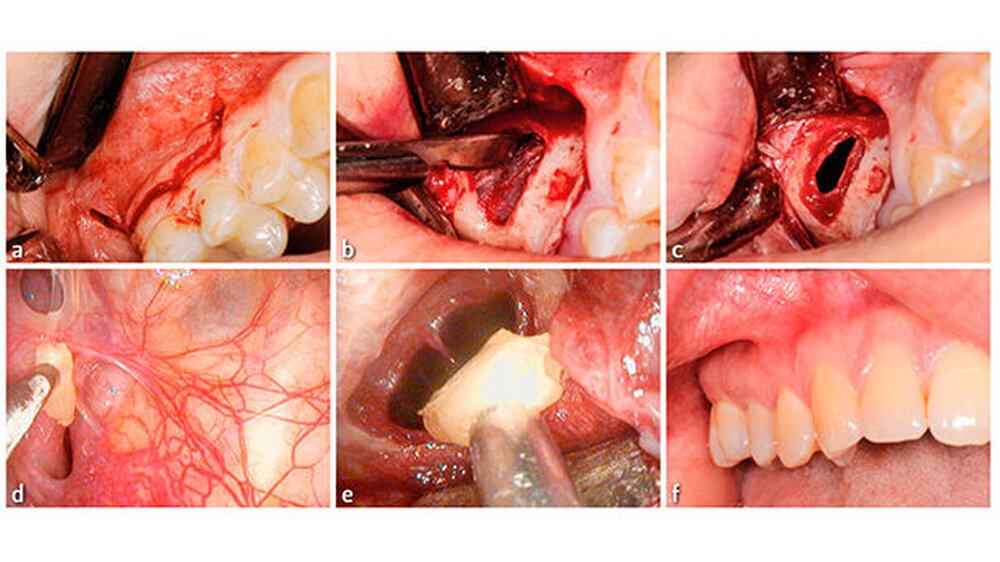

Nach ausführlicher Besprechung der Therapieoptionen mit der Patientin und der Aufklärung über mögliche Komplikation wurde eine chirurgische Entfernung des Wurzelrests vereinbart. Der Eingriff erfolgte nach präoperativer Gabe von Dalacin 300 mg 1 h präoperativ und über drei Tage postoperativ (anamnestisch berichtete die Patientin über eine frühere Amoxicillin-Unverträglichkeit) ambulant. Der Eingriff erfolgte in Lokalanästhesie mittels Septanest 1 : 200000. Der operative Zugang erfolgte mittels eines girlandenförmigen Paramarginalschnitts ca. 3 mm unterhalb des Sulcus innerhalb der Attached Gingiva mit mesialer und distaler Entlastung in regio 14–16.

Nach Abschieben des Mukoperiostlappens wurde der Knochen bis zur Schneider’schen Membran mittels Piezosurgery abgetragen. Es erfolgte ein Horizontalschnitt durch die Membran und damit die Eröffnung des Sinus maxillaris. Mittels eines flexiblen Endoskop konnte der Wurzelrest in regio des Ostium naturale visualisiert und mittels eines feinen Saugers adhäsiv aus der Kieferhöhle entfernt werden.

Die Kieferhöhle wurde mehrfach mit NaClLösung gespült und endoskopisch kontrolliert. Die Schneider’sche Membran wurde mit resorbierbaren Nähten 5.0 verschlossen und die Gingiva mit nicht resorbierbaren Einzelknopfnähten geschlossen (5.0 und 6.0). Postoperativ wurden Analgetika (Dafalgan 500 mg 111 für 3 d, Brufen 600 mg bei Bedarf), ein Antibiotikum (Dalacin C 300 mg 111 für 3 d) gegeben und eine Mundspüllösung rezeptiert (Chlorhexamed® FORTE 0,2 Prozent, täglich 2× den Mund für 1 min spülen). Um die Belüftung der Kieferhöhle zu gewährleisten, wurde ein Nasenspray abgegeben.

Außerdem wurde die Patientin darauf hingewiesen, wenn möglich nicht zu niesen oder zu schnäuzen (falls dies trotzdem erfolgt: ohne zugehaltene Nase oder zugehaltenen Mund) und für die nächsten fünf Tage auf sportliche Aktivitäten oder starken Wärmeeinfluss zu verzichten (Abb. 3).

Die erste postoperative Kontrolle erfolgte nach vier Tagen. Die Patientin war beschwerdefrei, und intraoral zeigte sich eine stadiengerechte Wundheilung. Die klinische Kontrolle war ohne pathologischen Befund. Die Rachenhinterwand war frei und zeigte keinen Schleim oder Eiterabsonderung des Sinus maxillaris. Zehn Tage postoperativ stellte sich die Patientin mit einer ebenso regelrechten Wundheilung vor, die Nähte konnten entfernt werden. Bei der 4-Wochen-Nachkontrolle zeigte sich eine feine, nicht entzündete Narbe im Bereich des Zugangs. Die röntgenologische Kontrolle zeigte eine gut belüftete rechte Kieferhöhle auf dem halbseitigen OPT.